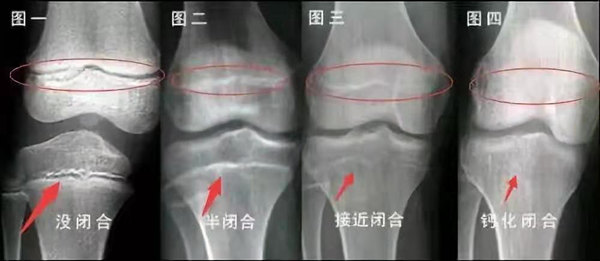

青少年一般什么時(shí)候骨骺閉合?

一般女孩是在16歲,男孩是在18歲。

一般來(lái)說(shuō),女孩的骨齡超過14歲,男孩的骨齡超過16歲,這時(shí)其骨骺線已接近閉合,基本沒有長(zhǎng)高的機(jī)會(huì)了。

因此,越早了解骨骺線閉合情況,越早干預(yù),孩子長(zhǎng)高的可能性越大。